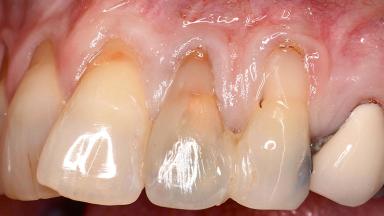

Early Implant Placement, Contour Augmentation, and Autologous Connective-Tissue Graft Using a Tunneling Technique to Replace an Upper Incisor with Generalized Gingival Recession

Variations in soft-tissue volume, evidenced either by an overabundance (Evian and coworkers 1993; Levine and McGuire1997; Dolt and Robbins 1997) or by a deficiency of soft or hard tissue can complicate implant-supported rehabilitations in the esthetic zone (Lorenzana 2008; Lorenzana and coworkers 2009). The present case illustrates the replacement of a failing upper left lateral incisor complicated by generalized severe gingival recession in the esthetic zone.

| Soft Tissue Anatomy | Intact | Defective | |

| Bone Volume | Horizontally and vertically sufficient | Horizontally deficient | Deficient vertically or deficient vertically AND horizontally |